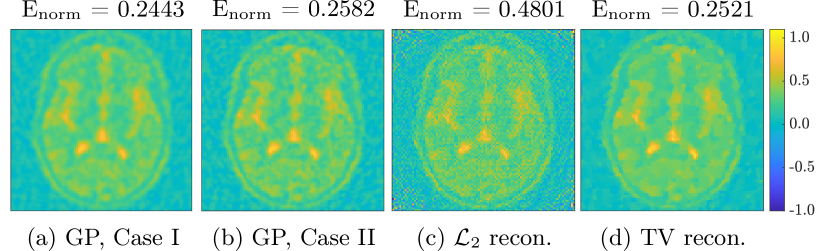

Next we compare the GP-based reconstruction with existing techniques— reconstruction (i.e., least squares) and the total variation (TV)- regularized reconstruction [17]. We explore iterative shrinkage-thresholding algorithms such as TwIST [18] to efficiently solve the TV-regularized inverse problem. The optimal value , for the TV regularization parameter , is chosen as the one yielding the lowest Enorm via a uniform grid search on (see Figure 5a). As a well-known challenge, the TV-based reconstruction quality is highly sensitive to the choice of , which makes it difficult for practical application in the absence of ground truth. In contrast, the hyperparameters in the GP approach are chosen based on more principled approaches such as maximizing the likelihood of the observed data, such that the workflow is more systematic and robust. Figure 5(b) further compares performance at different noise levels. The noise added to the measurements is similar to Case I, except for this study we let where , thus, as increases the variance of -s also increase ultimately leading to higher levels of heteroscedasticity. For Case II we assume -s are unknown, as before, and chose . We emphasize that even with the optimally chosen parameter for TV-regularized reconstruction with access to the ground truth, the GP-based approach can still achieve comparable and even better reconstruction, especially at higher noise levels. Figure 6 shows the corresponding reconstructions, and Figure 7 shows the posterior mean and standard deviation for both Case I and II for the middle slice of the brain image, which again emphasizes the superb capability of the GP approach for providing a quantifiable measure of the reconstruction uncertainty.